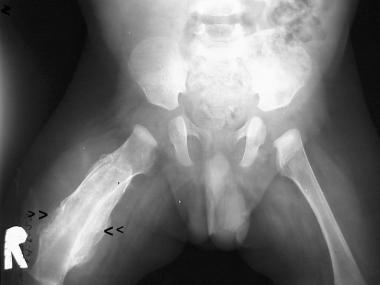

Dumbbell shaped mass extending from intra-abdominal into large exophytic perineal mass in a newborn.

may have cystic elements

sacrococcygeal teratoma

–> high rate of in utero hydrops and hemorrhage –> can be controlled at birth with immediate resection of exophytic component

rhabdomyosarcoma can also present as large pelvic mass but would be older child (2-6 years) and wouldn’t extend into perineum

infantile fibrosarcoma can have solid and cystic components in a newborn but more often in head/neck and extremities